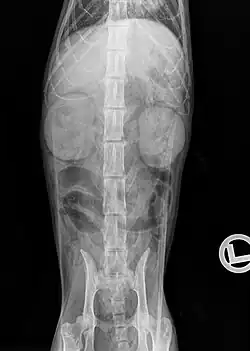

Radiographie

Un examen radiographique peut permettre de détecter des modifications de taille, d'opacité et de position des reins, et mettre en évidence certaines urolithiases : les calculs de struvite sont parfois visibles (phosphate de magnésium et d'ammonium) et les calculs d'oxalate de calcium sont opaques aux rayons X. Des minéralisations des tissus mous peuvent également être observées autre part, notamment en région sous-pleurale. Chez les chats fortement amaigris, ou dans le cas d'épanchement liquidien dans l'espace rétropérinéal, le contraste abdominal peut être diminué. L'urographie intraveineuse peut permettre de visualiser les voies urinaires, par injection d'un produit de contraste (p. ex. iopamidol ou iohexol) dans la circulation sanguine, qui est ensuite excrété par le rein. Cet examen est indiqué notamment pour la recherche d'une obstruction des voies urinaires, par des urolithiases par exemple, et de visualiser une éventuelle distension de la cavité pyélique qui en résulte (hydronéphrose)[27].